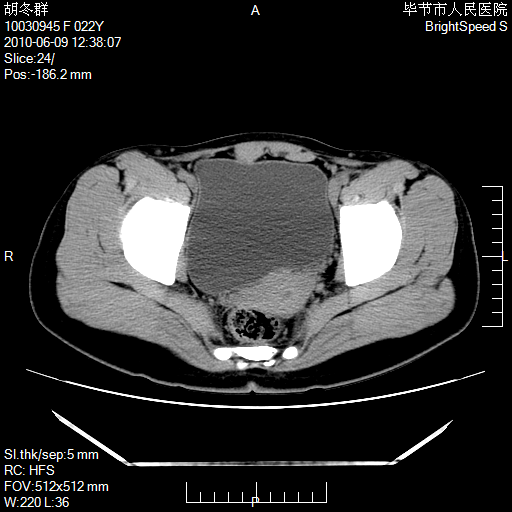

患者23岁,发现腹部包块3月。

左侧卵巢囊腺瘤或囊腺癌

盆腔内囊性占位性病变;考虑左侧卵巢囊腺瘤。

有分隔、壁薄,支持考虑左侧卵巢囊腺瘤。

左侧卵巢浆液性囊腺瘤。

有分隔、壁薄,支持考虑左侧卵巢囊腺瘤。排尿后,膀胱缩小,由于重力作用,肿块下移就到了膀胱位置,很好理解。